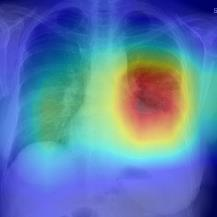

Thoracic disease detection from chest radiographs using deep learning methods has been an active area of research in the last decade. Most previous methods attempt to focus on the diseased organs of the image by identifying spatial regions responsible for significant contributions to the model's prediction. In contrast, expert radiologists first locate the prominent anatomical structures before determining if those regions are anomalous. Therefore, integrating anatomical knowledge within deep learning models could bring substantial improvement in automatic disease classification. This work proposes an anatomy-aware attention-based architecture named Anatomy X-Net, that prioritizes the spatial features guided by the pre-identified anatomy regions. We leverage a semi-supervised learning method using the JSRT dataset containing organ-level annotation to obtain the anatomical segmentation masks (for lungs and heart) for the NIH and CheXpert datasets. The proposed Anatomy X-Net uses the pre-trained DenseNet-121 as the backbone network with two corresponding structured modules, the Anatomy Aware Attention (AAA) and Probabilistic Weighted Average Pooling (PWAP), in a cohesive framework for anatomical attention learning. Our proposed method sets new state-of-the-art performance on the official NIH test set with an AUC score of 0.8439, proving the efficacy of utilizing the anatomy segmentation knowledge to improve the thoracic disease classification. Furthermore, the Anatomy X-Net yields an averaged AUC of 0.9020 on the Stanford CheXpert dataset, improving on existing methods that demonstrate the generalizability of the proposed framework.